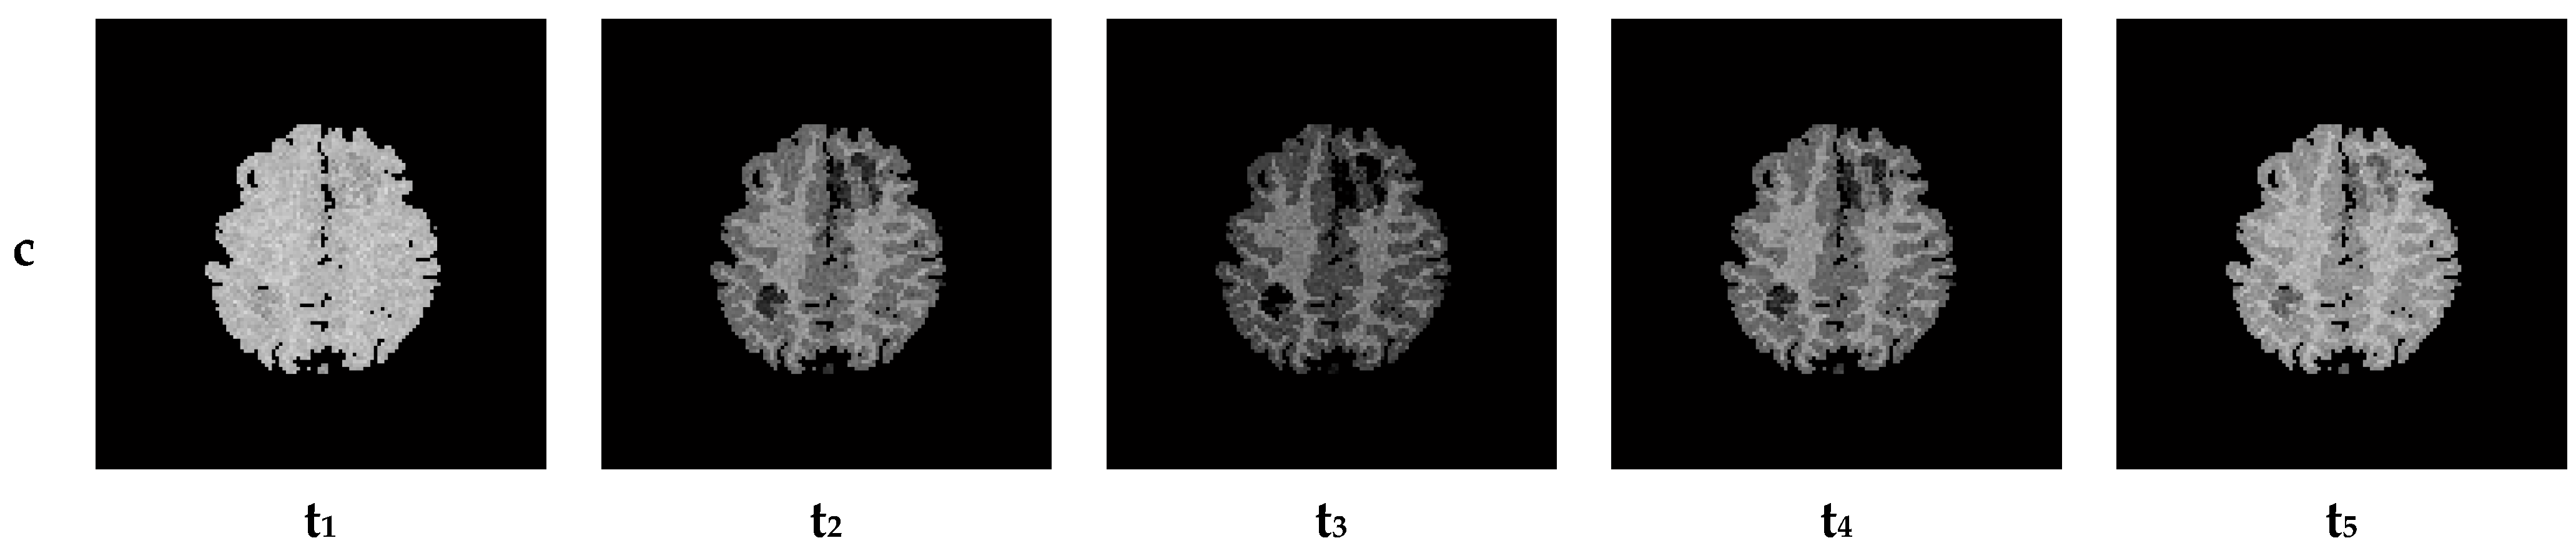

7. Results—Exemplary DSC-MRI Study Models